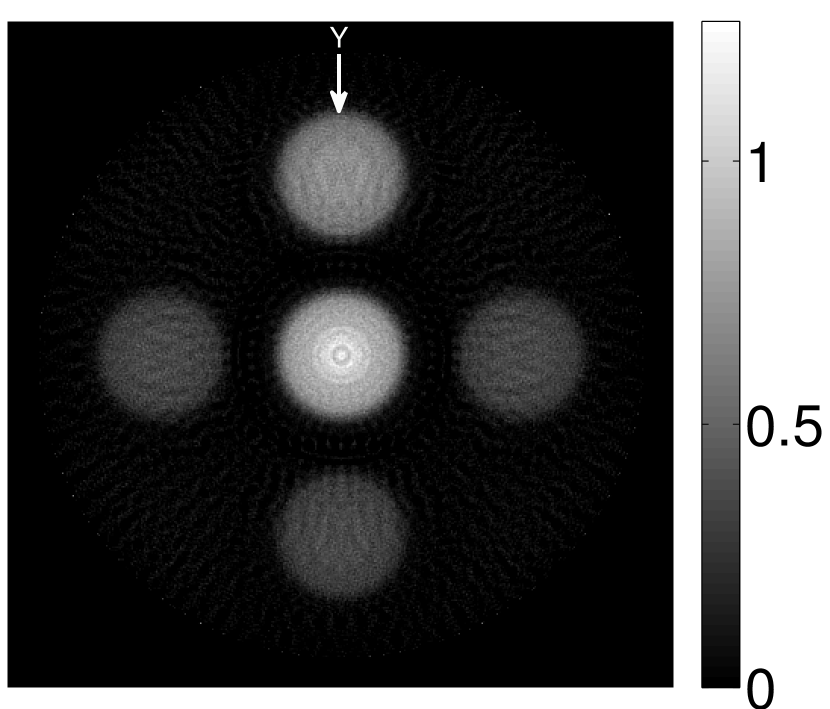

Figure 2(a) shows the image reconstructed by use of the conventional iterative method that utilized a system matrix based on EIR-2. Different values of the regularization parameter from the interval were considered. The reconstructed image with the value of that minimized the RMSE was chosen to represent the best performance of the conventional iterative method. Figure 2(a) and the profile in Figure 2(c) demonstrate that the use of an inaccurate EIR can result in strong artifacts and distortions in images reconstructed by use of the conventional methods.

When the VP algorithm was applied, different values of the regularization parameter from the interval and from the interval were considered. The image that minimized the RMSE was chosen and displayed in Figure 2(b). As revealed by this image and the profiles in 2(c), the VP algorithm yielded an image with fewer artifacts and distortions, and image fidelity was improved as reflected by the reduced RMSE.

Figure 7(a) reveals that use of the inaccurate EIR in the conventional iterative method created strong artifacts and distortions. Figures 7(b) confirms that the artifacts and distortions were significantly mitigated when the VP method was employed. Image profiles for both cases are shown in Figures 7(c). The overall accuracy of the recovered EIR, shown in Figure 7(d) and 7(e), was improved, but it contained spurious oscillations.